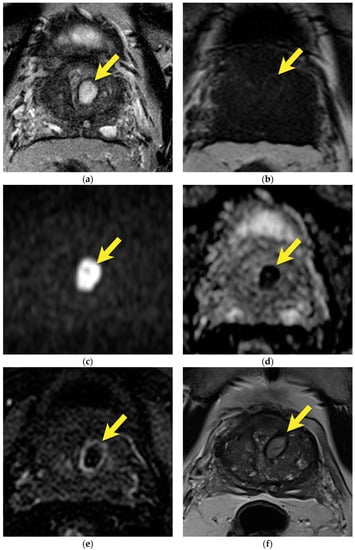

10. Prostatic Abscess